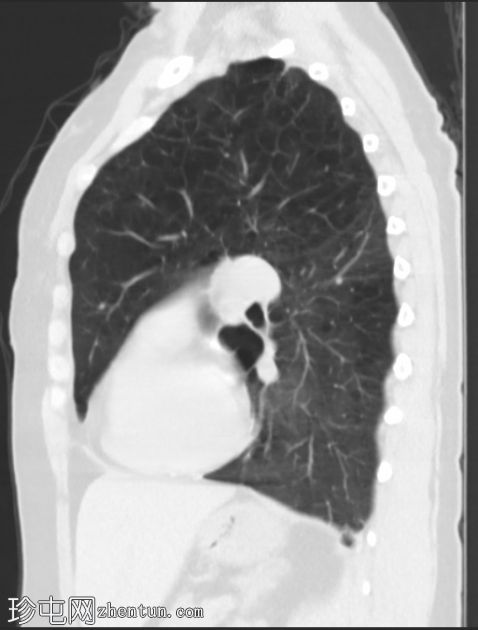

双侧肺(尤其是上叶)广泛融合性小叶中心型肺气肿。

左上叶肺瘢痕形成,可能是先前感染的后遗症。

双侧乳房植入。

早期小叶中心性肺气肿通常表现为小(<1 mm 至 3 cm)、圆形、均匀分布、边界不清的透亮区,可能出现在小叶中心动脉周围的次级肺小叶中央部分,而在严重的情况下,低衰减区会融合且不可分离,并且失去小叶中心分布。